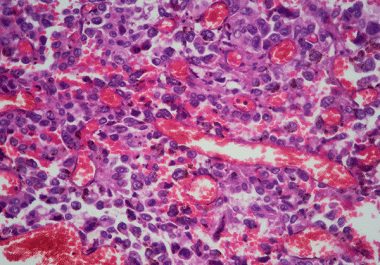

The FDA has approved amivantamab-vmjw, both alone and in combination with chemotherapy, for the treatment of certain non-small cell lung cancers. The U.S. Food and Drug Administration (FDA) has approved amivantamab-vmjw (Rybrevant), in combination...